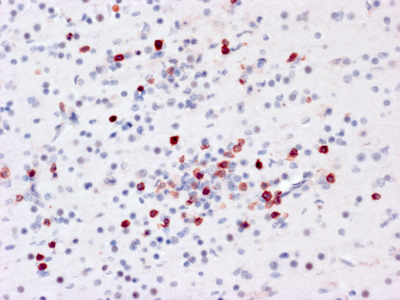

Figure 3A. Immunostain for CD3 of neocortical tissue from the brain of a child who died of Coxsackie viral encephalomyocarditis shows dense infiltration of lymphocytes (red).

Figure 3B. Immunostain for Coxsackie viral antigens shows staining of multiple neuroglial cells in both the nucleus and cytoplasmic processes.